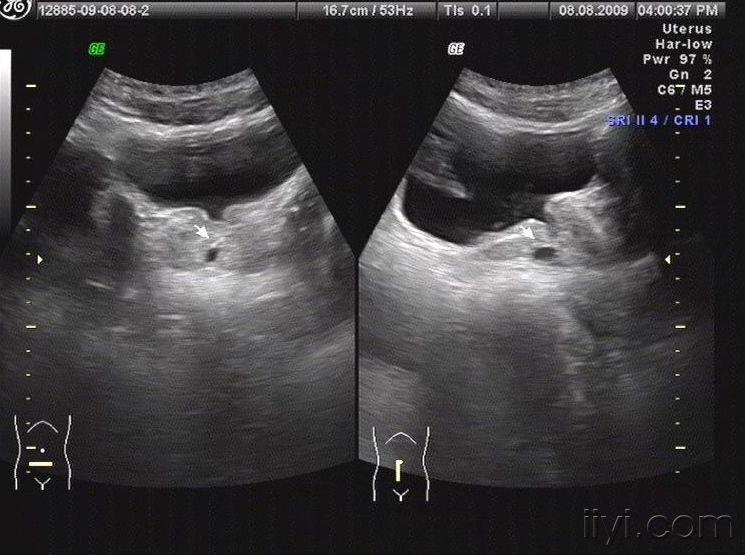

患者术前彩超显示前列腺明显增大

彩超显示前列腺4.2cm22正常吗

彩超提示:前列腺增生